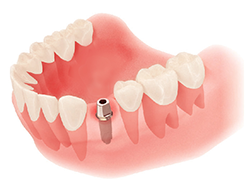

임플란트 식립

세밀한 치료계획 하에 임플란트 픽스쳐를 식립합니다. 통증은 생각보다 심하지 않습니다.